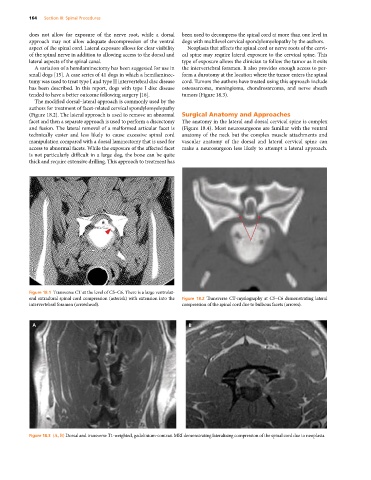

Figure 18.3 (A, B) Dorsal and transverse T1‐weighted, gadolinium‐contrast MRI demonstrating lateralizing compression of the spinal cord due to neoplasia.